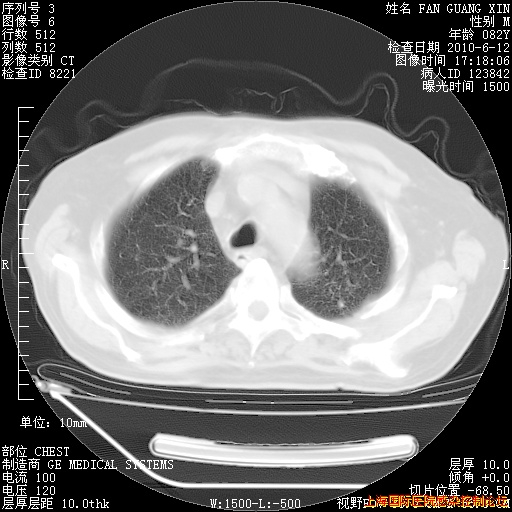

6月12日纵膈窗